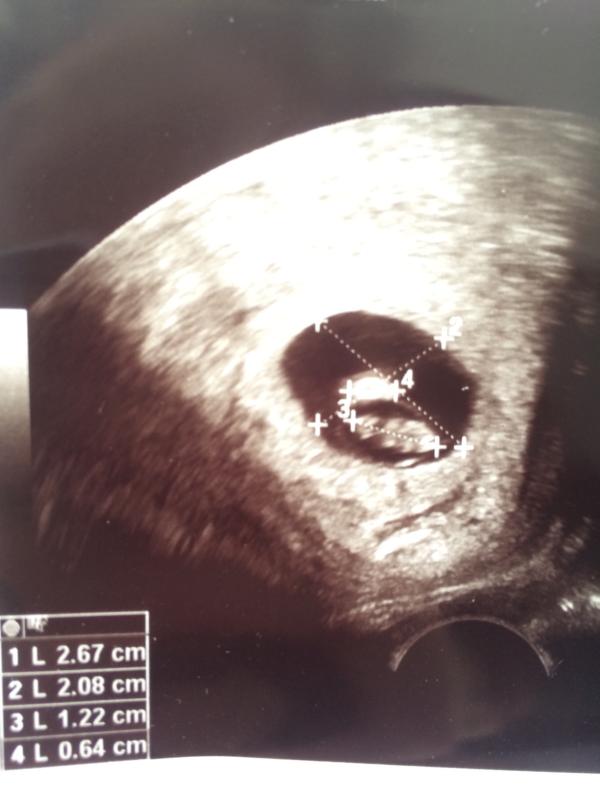

Было первое УЗИ несколько дней назад. И вот лежу я, смотрю на эту бусинку и почему-то кажется, что это мальчик. Ясное дело, что там не видно ещё ничего, но теперь не покидает это чувство.